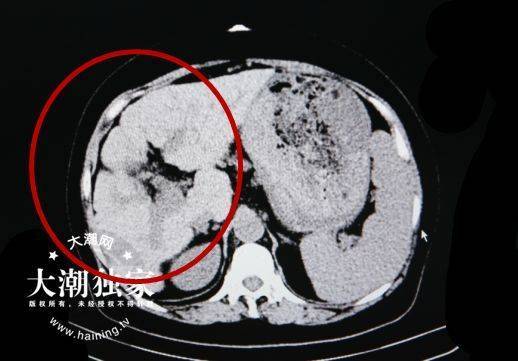

王女士腹部ct检查报告(红圈为肝脏所在位置)